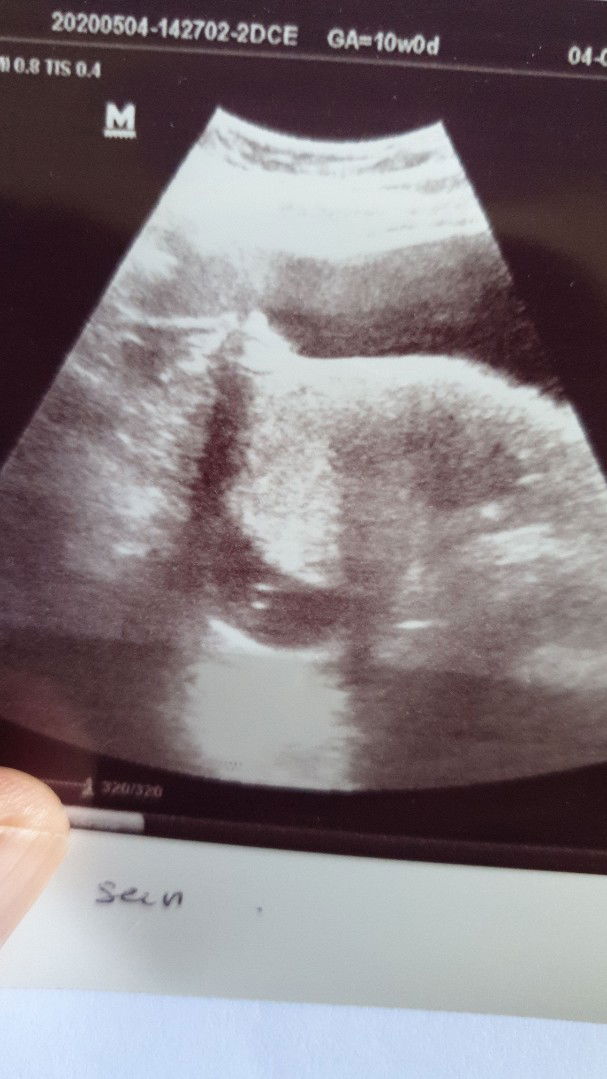

10 week pregnancy

Salam sejahtera semua.. saya baru ke pergi scan baby.. dri scan doktor kata kantung sya xnmpk baby.. sape ade pengalaman mcmni.. apa jdi dengan kandungan bgi yg berpengalaman mcmni.